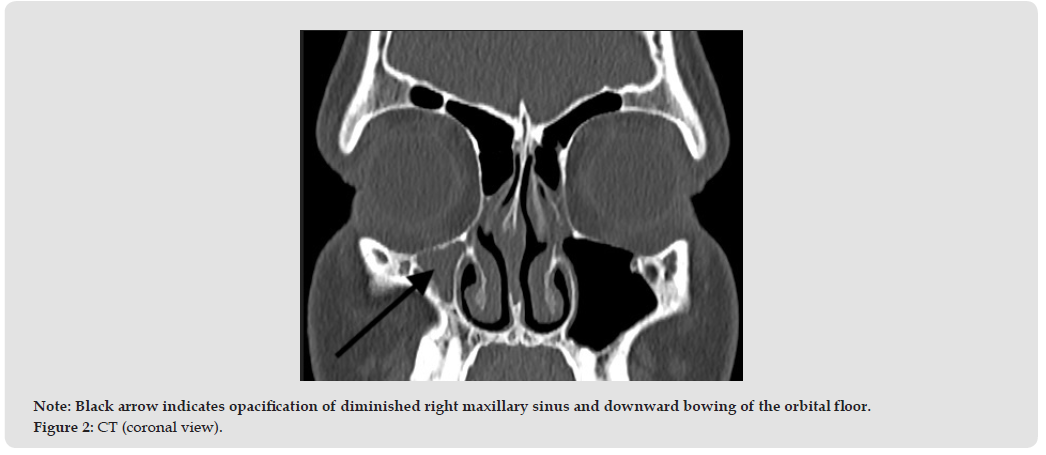

A 17- year-old boy was admitted to our department for sinus surgery. He reports a history of recurrent nasal congestion on the right side, postnasal drip and weakened sense of smell for 3 years. There were no complaints of pain. CT imaging showed a diminished right maxillary sinus, with loss of continuity of its medial wall and a thickening of its mucosa (Figures 2 & 3). The osteomeatal complex on the right side was narrowed, on the left side partially blocked. There was a slightly thickened mucosa of the right ethmoidal cells. A right-sided antrotomy was performed under general anesthesia. There was also the lateralization of the uncinate process. After uncinectomy the ostium of the right maxillary sinus was opened and widened. A thick, mucous discharge was removed from the interior of the sinus. The sinus was rinsed. No complications were observed in the perioperative period. No facial deformities were observed despite typical abnormalities for SSS in CT images. The child’s follow-up shows no progression of changes in the craniofacial bones.